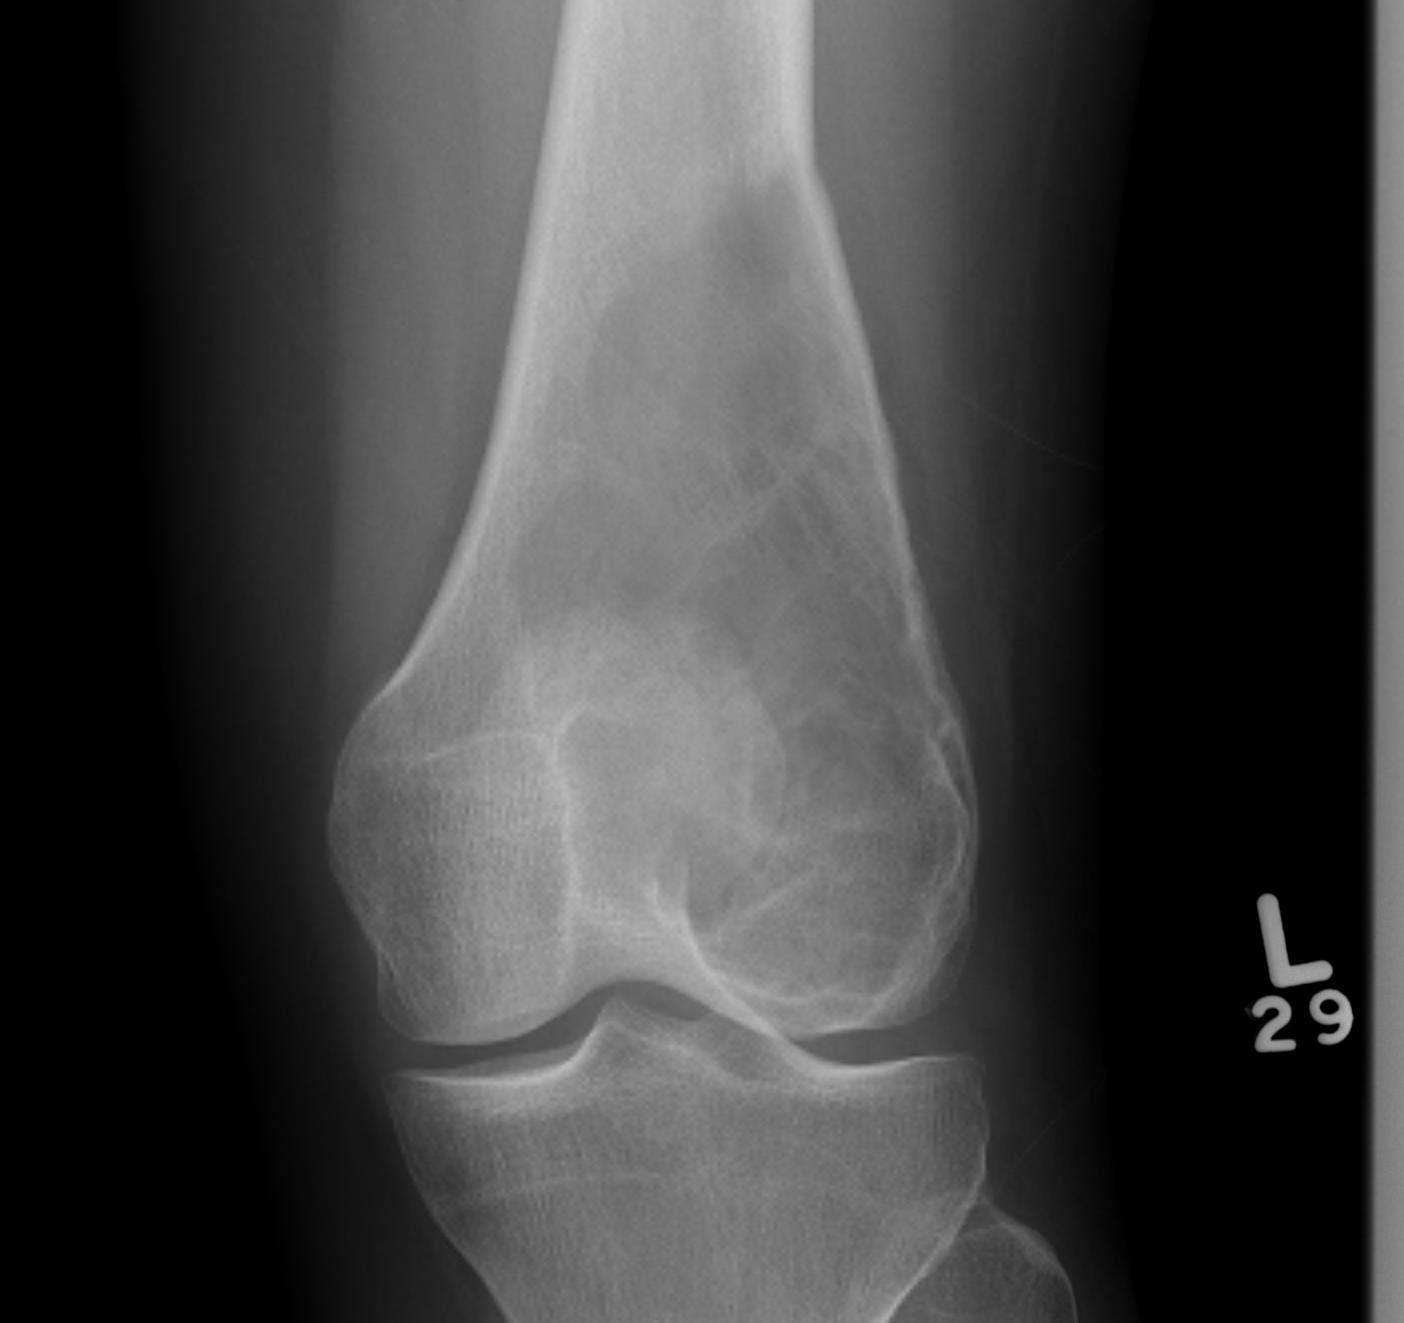

X-ray

Multi-loculated expansile lesion with cortical thickening

Often fail to make definitive diagnosis on xray